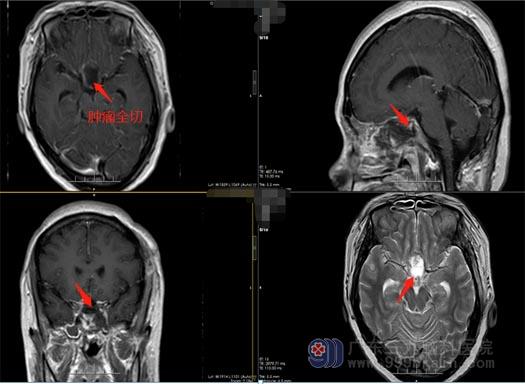

陈阿姨的症状非常典型,结合影像学检查,外五科治疗团队很快就为陈阿姨制定了手术方案。由鲁明副院长主刀,在全麻下为陈阿姨行“内镜经鼻鞍结节脑膜瘤切除术”,手术过程顺利,术后的陈阿姨恢复良好。

对于此疾病,手术是最佳的治疗手段。手术方式有多种,神经外五科最常选择的是经鼻蝶入路,此手术方式为微创,对于鞍内和鞍旁脑膜瘤具有明显优势,与传统开颅手术相比,避免了额窦的开放、颞肌的损伤,减轻了脑组织的牵拉损伤,术后相关并发症少;优先的颅底操作,便于处理肿瘤基底血供,减少术中出血;内镜直视下操作视野清晰,局部结构放大,多角度观察,可以减轻对颅底中心周围血管神经的激惹,能够直视视神经、视交叉、垂体柄等,减少术中损伤;同时能够切除受侵犯的骨质及脑膜,提高肿瘤的全切率,缩短手术操作时间,患者住院周期短,恢复快。